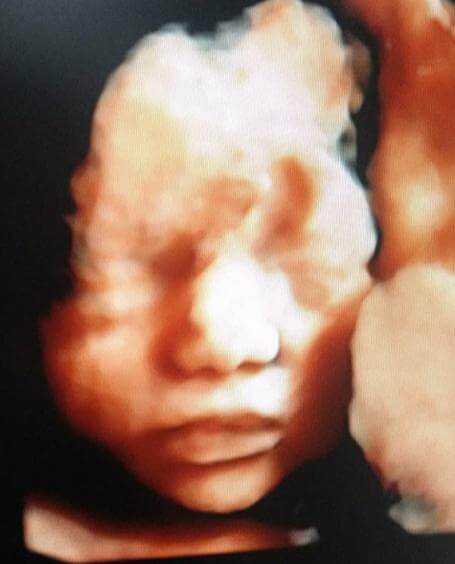

Realiza tamizaje de Síndrome de Down (primer trimestre), alteraciones estructurales (segundo trimestre) y vigilancia del crecimiento (tercer trimestre) a través de Ultrasonido de alta definición, Doppler, 3 y 4 dimensiones. Predicción, prevención y tratamiento especializado de Preeclampsia, parto pre-termino, diabetes gestacional y manejo de enfermedades crónicas durante el embarazo.

Acudir con un Médico Materno Fetal (especialista de tu bebé en el útero) por lo menos en 3 Ultrasonidos Fetales Especializados (para detección, prevención y seguimiento de etapas específicas de tu embarazo) te brinda mayor seguridad para ti y tu bebé.